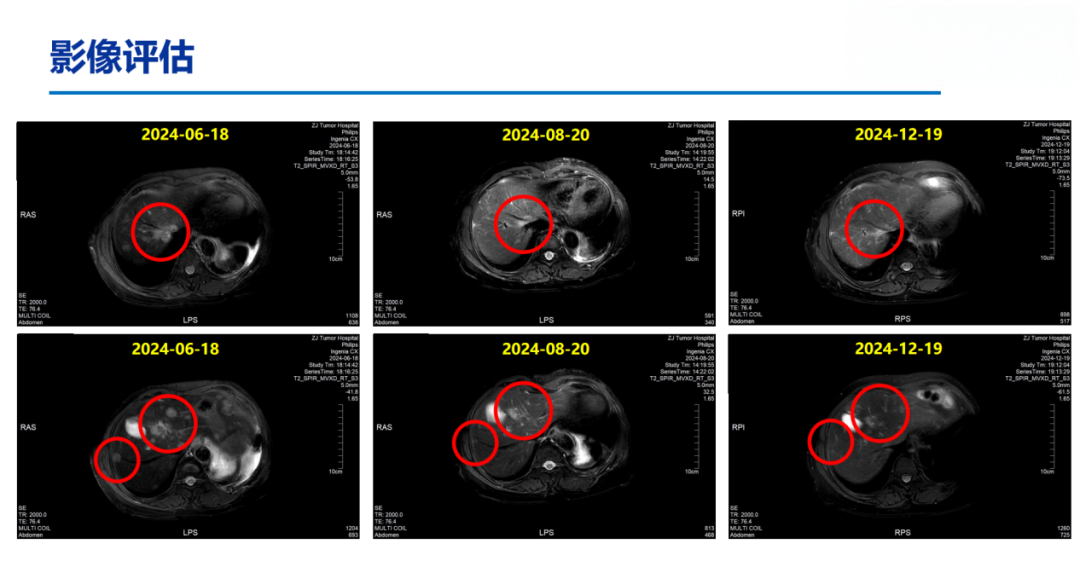

2024-06-18上腹部MR:乳腺癌肝转移化疗后复查,对照2024.03.21MR:肝多发转移瘤,较前增多、增大。部分胸椎异常信号,考虑转移,较前相仿。

DB-04研究结果显示,在总人群中,T-DXd组的中位总生存期较化疗组显著延长;基于该研究结果,国内外多项权威指南已一致推荐T-DXd作为HER2低表达晚期乳腺癌的标准治疗方案,尤其适用于既往接受过治疗的患者。基于DB-04的研究数据、国内外指南推荐及其可及性,患者于2024-07-08至2025-02-25予11周期“德曲妥珠单抗300mg,q3w”治疗,2周期后PR。

患者于2010年5月行左侧乳腺癌根治术,术后接受辅助化疗及他莫昔芬内分泌治疗,疾病稳定长达10年。2020年出现胸壁及淋巴结转移,后历经多线治疗,包括来曲唑治疗、化疗及CDK4/6抑制剂维持,疾病仍持续进展。基于DB-04研究的优异数据,患者于2024年7月启动二线T-DXd单药治疗,2周期后即达PR,显示出T-DXd在HR+/HER2低表达人群中的高效性。

同时在T-DXd治疗过程中,患者于第11周期后出现右肺下叶炎症,经影像学评估确诊为1级间质性肺病。我们立即启动大剂量甲泼尼龙治疗,后逐步减量,ILD在22天内明显缓解,45天内基本消失。在确保ILD完全控制后,我们于2025年5月再启动T-DXd治疗,患者持续获益,影像学评估持续PR。该病例充分体现了在T-DXd使用过程中ILD这一关键不良反应的可管理性。通过早期识别、及时干预、规范减量和再挑战,患者不仅安全度过风险期,还继续从T-DXd治疗中持续获益。

本病例中的患者为HR+/HER2低表达晚期乳腺癌,既往经内分泌治疗、化疗及CDK4/6抑制剂治疗后出现疾病进展,符合DB-04研究患者的入组条件且2024年T-DXd已经在我国获批HER2低表达领域的适应症,并实现药物可及。本例患者在接受T-DXd治疗2周期后即达PR,目前PFS已超过20个月且仍在持续接受治疗,这一案例进一步支持了T-DXd在HER2低表达晚期乳腺癌中的应用。